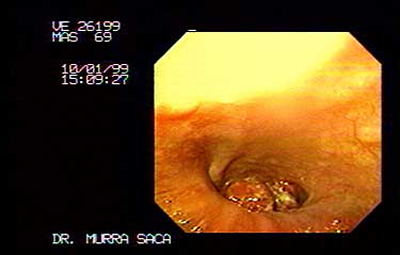

Imagen del cardias, Paciente Masculino 69 años:

Con disfagia progresiva, perdida de peso 20 libras y sialorrea, presenta Carcinoma del cardias y fondo, ver imagenes siguientes.